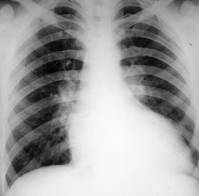

HIPERTROFIA VS

rotunjirea arcului inferior stâng cu pulsatii ample la acest nivel

accentuarea butonului aortic datorita aportului sanguin crescut

DILATAŢIA VS

alungirea arcului inferior stâng cu marirea diametrului transversal

scaderea pulsatiilor la acest nivel

accentuarea butonului aortic

configuratie aortica tipica